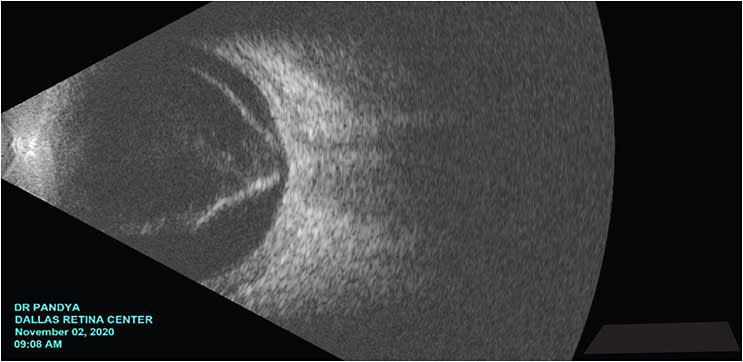

In traumatic retinal detachments, it is important to assess pupillary dilation, baseline inflammation, and lens status. Traumatic events can lead to sequelae of intraocular inflammation (corneal edema, posterior synechiae) and lens opacification. These changes can limit direct visualization of the posterior segment.

All surgical procedures have risks and side effects. Vitrectomy leads to cataract progression and may cause ocular hypertension. Chronic silicone oil tamponade can result in silicone oil migration into the anterior chamber with emulsification (reverse hypopyon). Perfluorocarbon should never purposefully be kept within the vitreous cavity, as this can result in inflammation. Other complications include secondary epiretinal membrane, optic neuropathy, and recurrent retinal detachment.

It is also important to appreciate the emotional aspects of vision loss. Their funnel retinal detachments may have an unfavorable configuration, and may be inoperable. Surgical intervention has the risk of leading to worsening vision. Always consider the psychological aspects of going from light perception (LP) to no light perception (NLP).